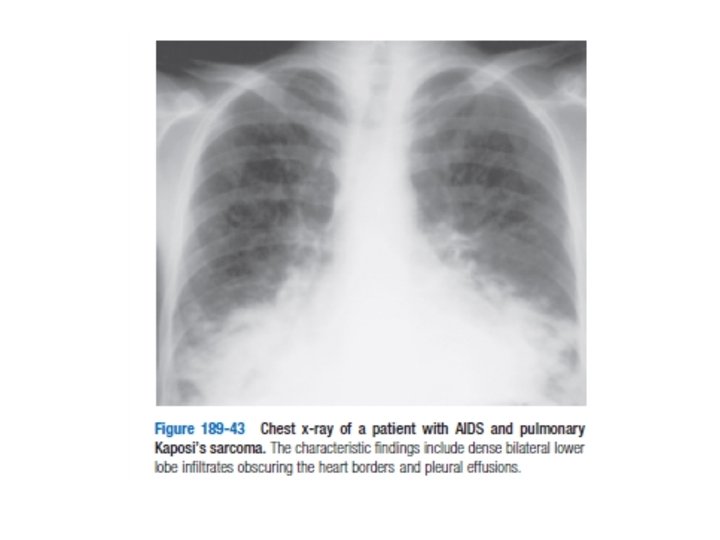

PULMONER KOMP. • İlerlemiş hastalık durumunda; Aspergillus ve C. Neoformansa bağlı fungal pnömoniler ortaya çıkar • Non-enfeksiyoz patolojiler – Kaposi sarkom, lenfositik interstisiyel pnömoni • CD 4 50 altına düştüğünde CMV, MAK pnömonileri ortaya çıkar

KUTANÖZ KOMP. Kaposi sarkomu; • Homoseksüel erkeklerde sıktır • Ciltte ağrısız, kabarık, kahve-mor renkli papüller ve nodüller – Nadiren difüz iç organ tutulumu olabilir • Prognozu göstermez kozmetik açıdan kriyoterapi& ablasyonla tedavi edilebilir – Diffüz tutulum vinkristin, vinblastin, doksurobsin